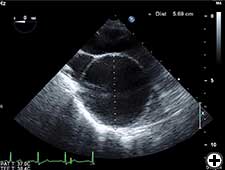

- Choose an appropriate diameter Dacron tube graft, for example, 1.5-2 cm less the diameter of ascending aorta. In this patient we used 3.8 cm Dacron tube graft when proximal and distal ascending aorta were 5.4 cm and 5.69 cm respectively on preoperative TOE (Figures 3 & 4).